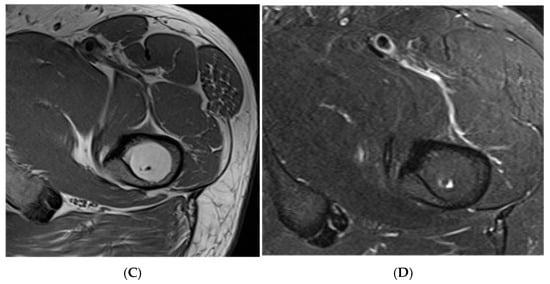

Figure 19.

Pars defect assessment CT image (A) and chemical shift in-phase (B) and out-of-phase (C), showing pars defect of L5 (arrow).

Figure 20.

Pars defect assessment sagittal CT image (A) and chemical shift in-phase (B) and out-of-phase (C), showing intact pars of L4 (arrow).

Figure 21. Focal marrow hyperplasia in L4. Sagittal T1 (A), T2 (B), CT (C), and chemical shift (D,E), showing heterogeneous signal on T1 and T2 and sclerosis on CT with significant signal drop on chemical shift images (D,E). - Characterising Indeterminate Marrow Lesions: In patients with cancer, incidental marrow lesions often cause clinical concern. CSI helps identify those lesions with retained fat, reducing the need for biopsy or further imaging such as bone scan or positron emission tomography (PET) [39] (Figure 18).

- On a slightly different theme, whilst not strictly utilising the SI drop-off calculations, chemical shift imaging in itself has been demonstrated to assess for and evaluate pars defects. In a cohort of 70 patients, chemical shift MRI effectively identified both intact and defective pars interarticularies, with out-of-phase imaging slightly better for detecting defects and in-phase imaging better for confirming intact pars. Although differences were not statistically significant, the technique demonstrated strong intra- and interobserver reliability and offers a fast, reliable complement to conventional MRI [41] (Figure 19 and Figure 20).